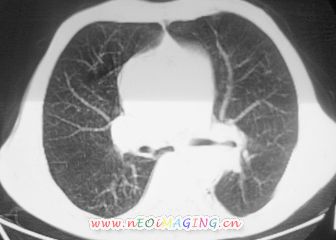

以下是引用卜一在2007-10-7 9:38:00的发言:[br]左下肺胸膜下团片影,内见含气支气管像,临近胸膜未见增厚。多考虑:1 左下肺炎症,建议消炎后复查!2 不除外肺隔离症合并感染!